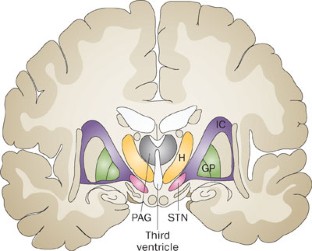

Deep brain stimulation (DBS) is an expanding field in neurosurgery and has already provided important insights into the fundamental mechanisms underlying brain function. One of the most exciting emerging applications of DBS is modulation of blood pressure, respiration and micturition through its effects on the autonomic nervous system. DBS stimulation at various sites in the central autonomic network produces rapid changes in the functioning of specific organs and physiological systems that are distinct from its therapeutic effects on central nervous motor and sensory systems. For example, DBS modulates several parameters of cardiovascular function, including heart rate, blood pressure, heart rate variability, baroreceptor sensitivity and blood pressure variability. The beneficial effects of DBS also extend to improvements in lung function. This article includes an overview of the anatomy of the central autonomic network, which consists of autonomic nervous system components in the cortex, diencephalon and brainstem that project to the spinal cord or cranial nerves. The effects of DBS on physiological functioning (particularly of the cardiovascular and respiratory systems) are discussed, and the potential for these findings to be translated into therapies for patients with autonomic diseases is examined.

DBS of the posterior hypothalamus, subthalamic nucleus (STN) and periaqueductal grey (PAG) can cause changes in cardiovascular indices at rest and during postural challenge

In patients with chronic pain or movement disorders, lung function improvements seemingly unrelated to amelioration of the underlying syndrome can occur with DBS of the STN or PAG